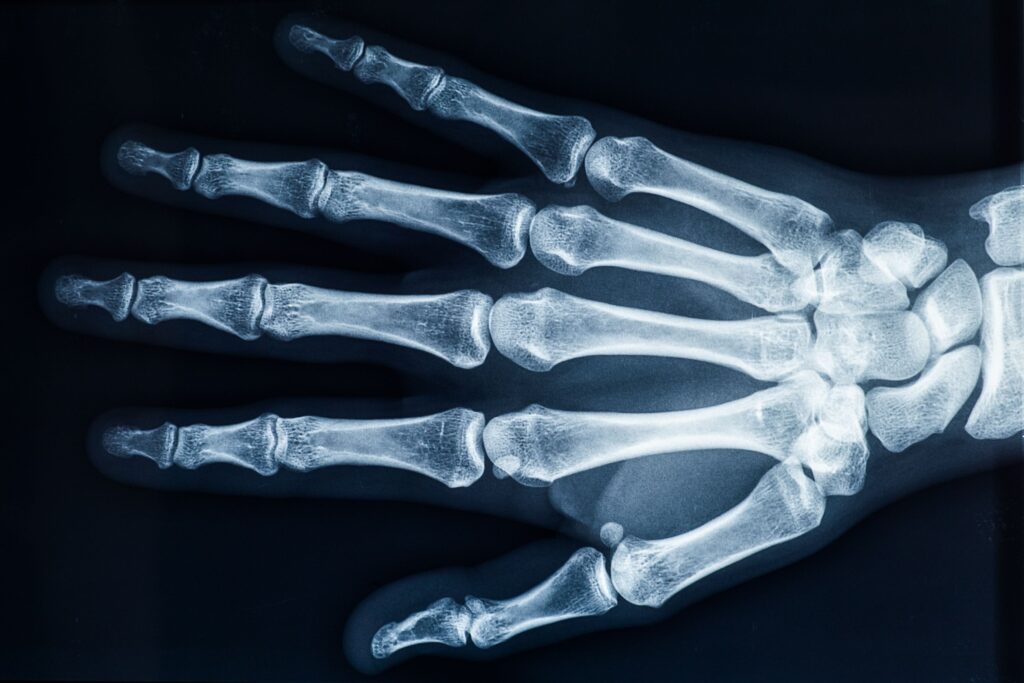

レントゲン検査

必要に応じてレントゲン検査を行い、手や指の骨や関節の状態を確認します。主に、次のような点について確認します。

・骨の状態

・関節まわりの変化

・腱やその周囲の様子

レントゲン検査では分かりにくい部分については、症状や経過を踏まえ、エコー検査をご案内することがあります。エコー検査では、骨の表面や筋肉・腱の状態などを確認することができます。